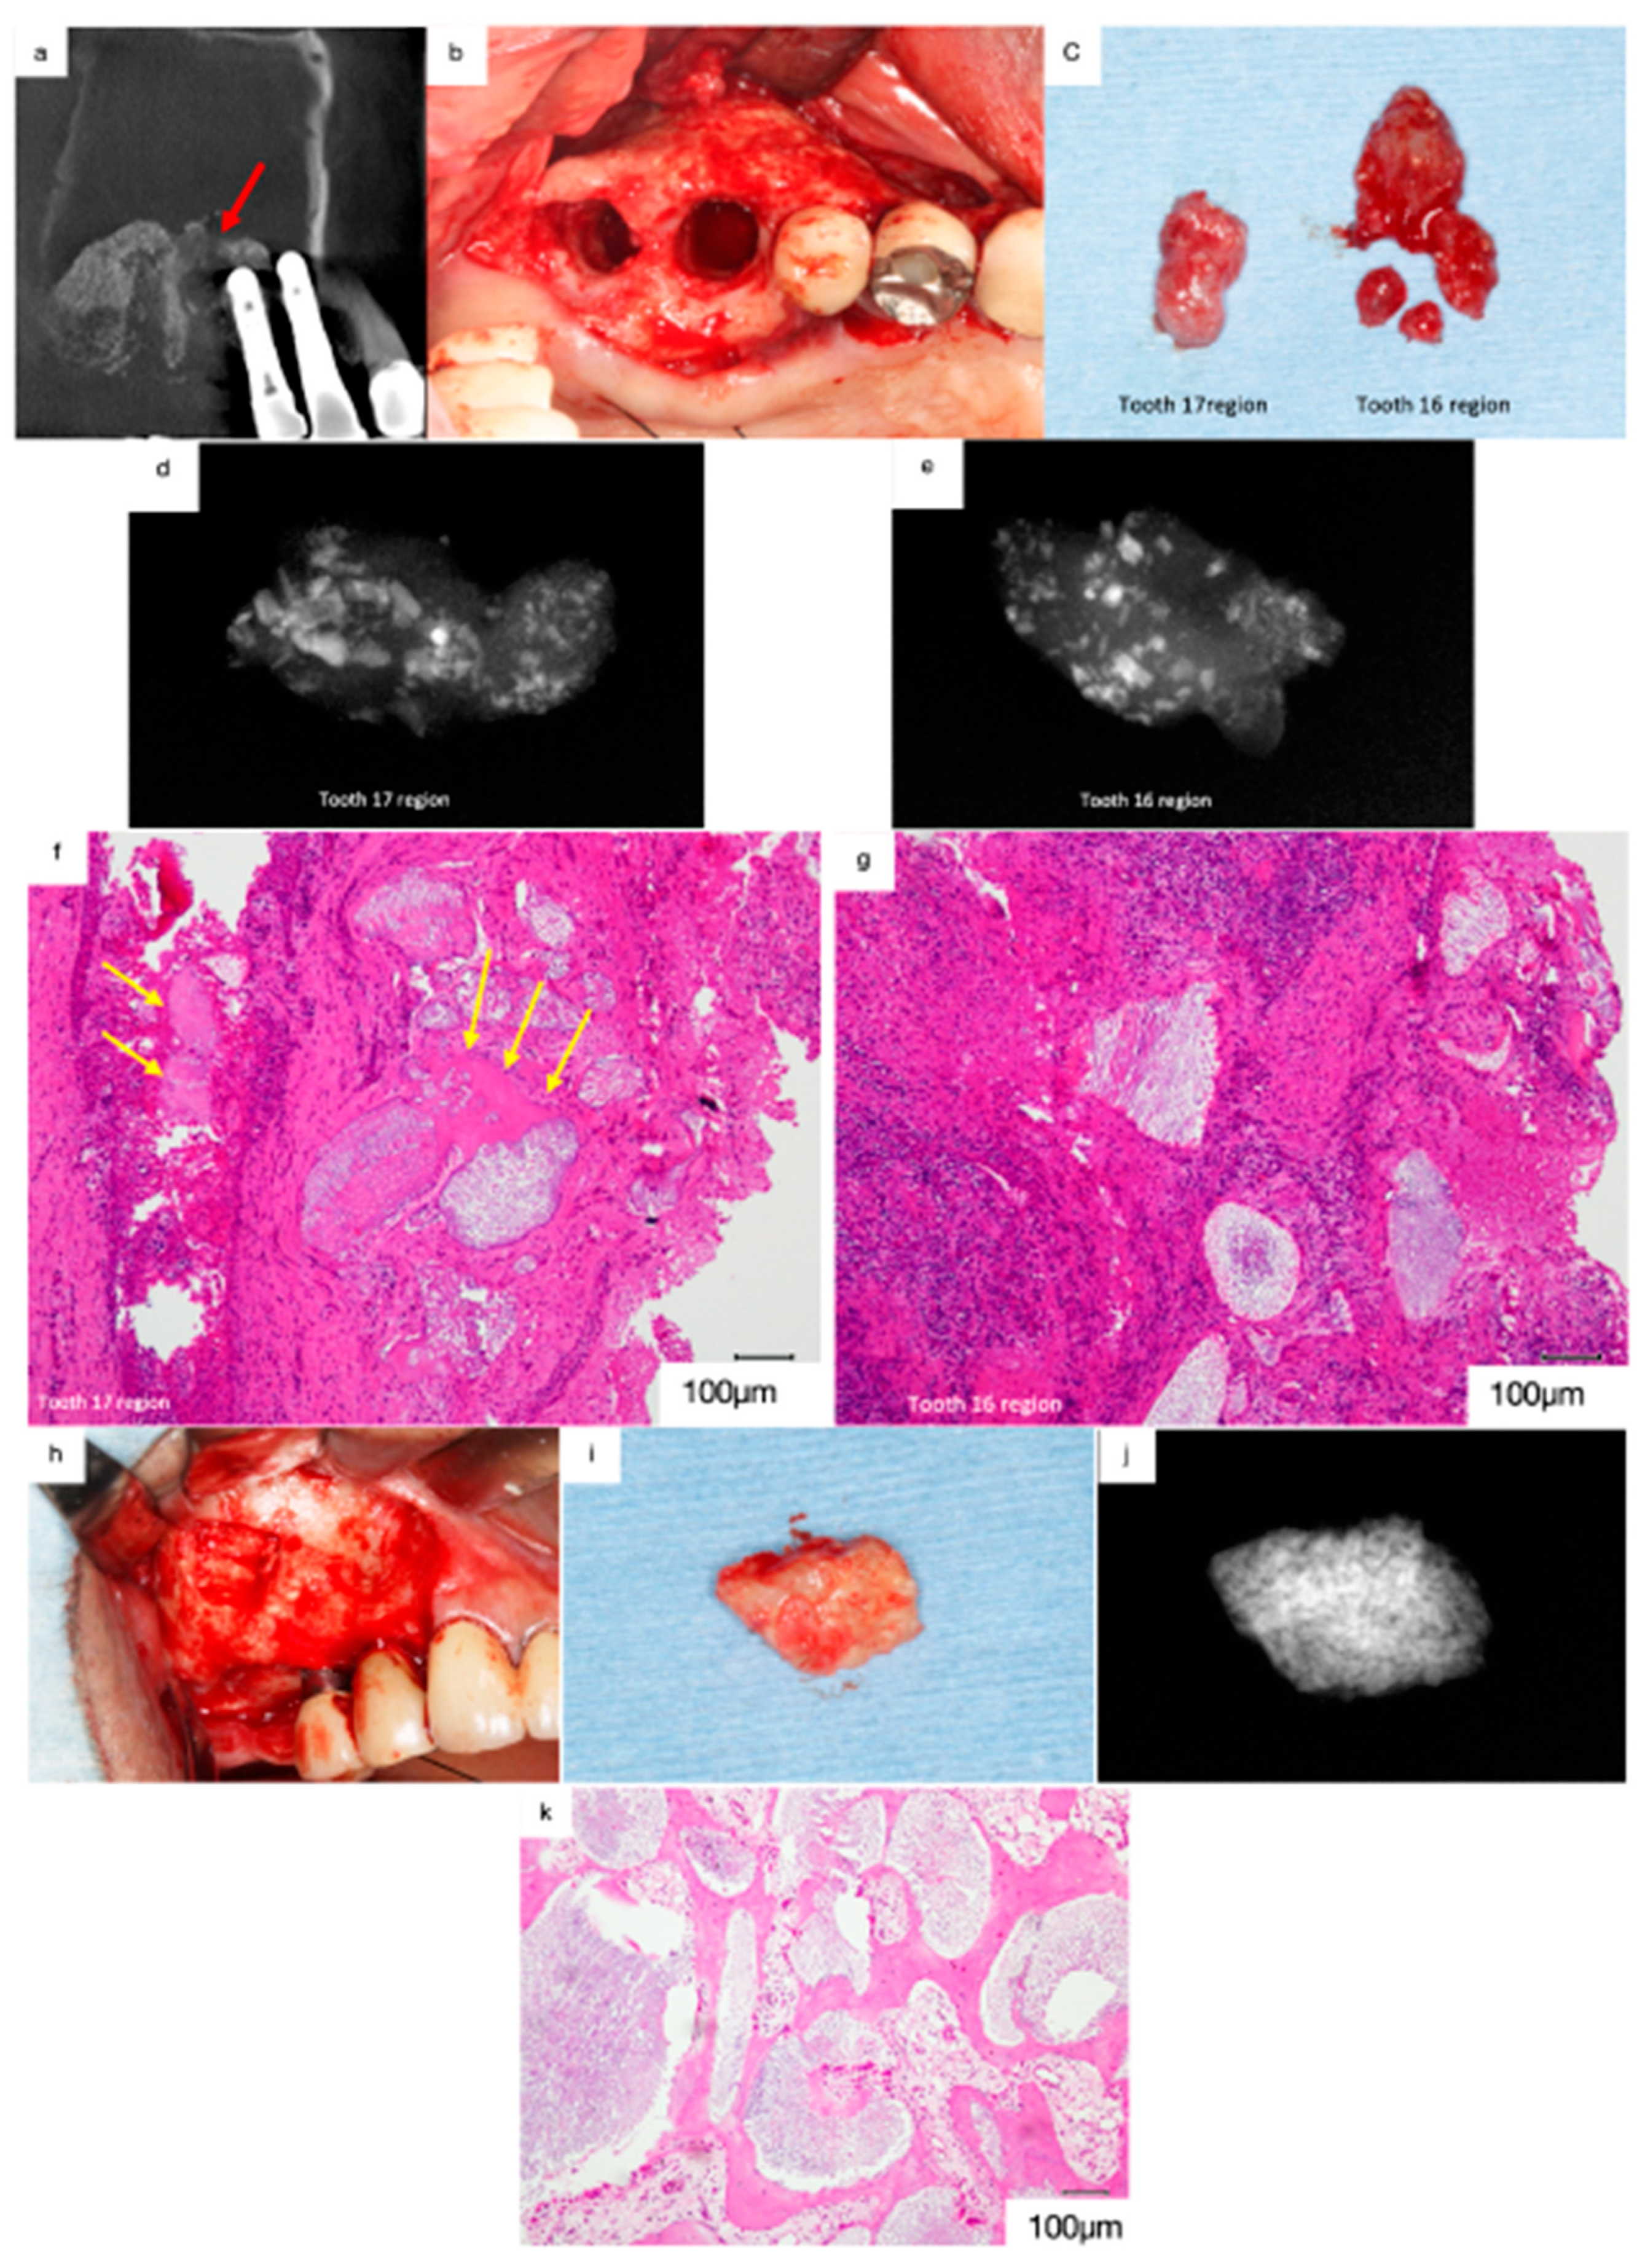

Figure 9.

(a) Mediodistal section of the CT image acquired at the first visit. Prominent swelling of the sinus membrane can be observed, and no pneumatic space is present in the maxillary sinus. Artificial bone is absent at the floor of the maxillary sinus near 16 (red arrow). (b) The soft tissues surrounding 17 and 16 were removed. (c) Artificial bone granules were observed in the removed soft tissues. (d) Radiograph of the removed soft tissues surrounding 17. Radiopaque particles of various sizes were observed in the soft tissue. (e) Radiopaque particles of various sizes can be observed in the soft tissue surrounding 16. (f) Histological decalcified specimen of the soft tissue surrounding 17 (haematoxylin and eosin staining). Bio-Oss granules can be observed among the fibrous connective tissues with moderate infiltration of inflammatory cells, and only small bone tissues remain beside the Bio-Oss granules (yellow arrows). (g) Severe infiltration of inflammatory cells was observed in the fibrous connective tissue surrounding 16, and no live bone remains around the Bio-Oss granules. (h) Bone biopsy performed on the lateral wall. (i) White particles are grossly embedded in the harvested hard tissue. (j) Radiograph of the specimen showing dense radiopaque particles in the harvested tissue. (k) The demineralised histological specimen (H.E. staining) shows that newly formed live bone is present adjacent to the Bio-Oss granules, and many foreign body giant cells can be observed around the Bio-Oss granules.

The removal of the soft tissue surrounding 17 and 16 revealed artificial bone granules (Figure 9b,c). Radiographs acquired subsequently revealed radiopaque particles of varying sizes within the tissues (Figure 9d,e). The demineralised histological specimen (H&E staining) revealed the presence of Bio-Oss granules in the fibrous connective tissues (Figure 9f,g). Moderate infiltration of inflammatory cells was observed in the fibrous connective tissues in the regions surrounding 17, and only small bone tissues were observed beside the Bio-Oss granules (Figure 9f, yellow arrows). In contrast, severe infiltration of inflammatory cells was observed in the regions surrounding 16, and no live bone was observed around the Bio-Oss granules (Figure 9g). These findings suggest that peri-implantitis disrupted osseointegration and that Bio-Oss granules were isolated from the newly formed bone tissue. Furthermore, the infection spread to the maxillary sinus through the Bio-Oss granules in the regions surrounding 16, leading to sinusitis.

A bone biopsy was performed on the lateral wall after receiving consent from the patient (Figure 9h,i). Radiographs of the harvested specimen revealed dense radiopaque particles (Figure 9j). The demineralised histological specimen (H&E staining) revealed the presence of newly formed live bone adjacent to the Bio-Oss granules (Figure 9k). Furthermore, numerous foreign body giant cells were observed around the Bio-Oss granules, suggesting that the biological reaction to the Bio-Oss granules had persisted for 10 years postoperatively. Thus, non-absorbable bone materials are associated with a risk of inducing sinusitis in patients with peri-implantitis when used as bone material for sinus floor elevation.